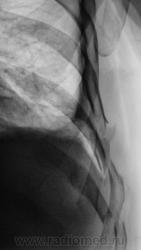

- https://radiomed.ru/sites/default/files/styles/case_slider_image/public/user/12/2.pb130018.jpg?itok=qpNgo3K0

- https://radiomed.ru/sites/default/files/styles/case_slider_image/public/user/12/3.pb130020.jpg?itok=ZQIONPdk

Я так понимаю , что справа - это случайная находка ( C-r нижнедолевого бронха , осложненный субателектазом правого легкого и правосторонним гидропневмотораксом) ?

Нет. Это ДТП.

Снимок был сделан на передвижке, качества ниже "хренового", но уже тогда газ в плевральной полости справа был, была с обеих сторон огроменная подкожная и межмышечная эмфизема.